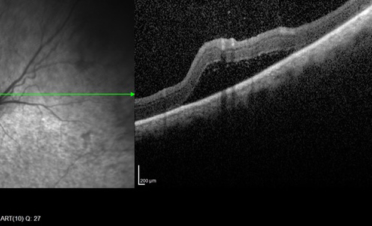

OCT del segmento posterior

Haremos una OCT del segmento posterior cuando necesitemos:

- Medir las diferentes capas de fibras de la retina y el nervio óptico. Con este tipo de OCT realizamos un corte histológico en vivo de las diferentes capas del fondo ocular: retina, nervio óptico y coroides pudiendo llegar incluso hasta la esclerótica.

- Valorar cambios en la estructura, como por la presencia de exudados, hemorragias, degeneraciones,

edema, membranas epirretinianas, anomalías del vítreo posterior ….